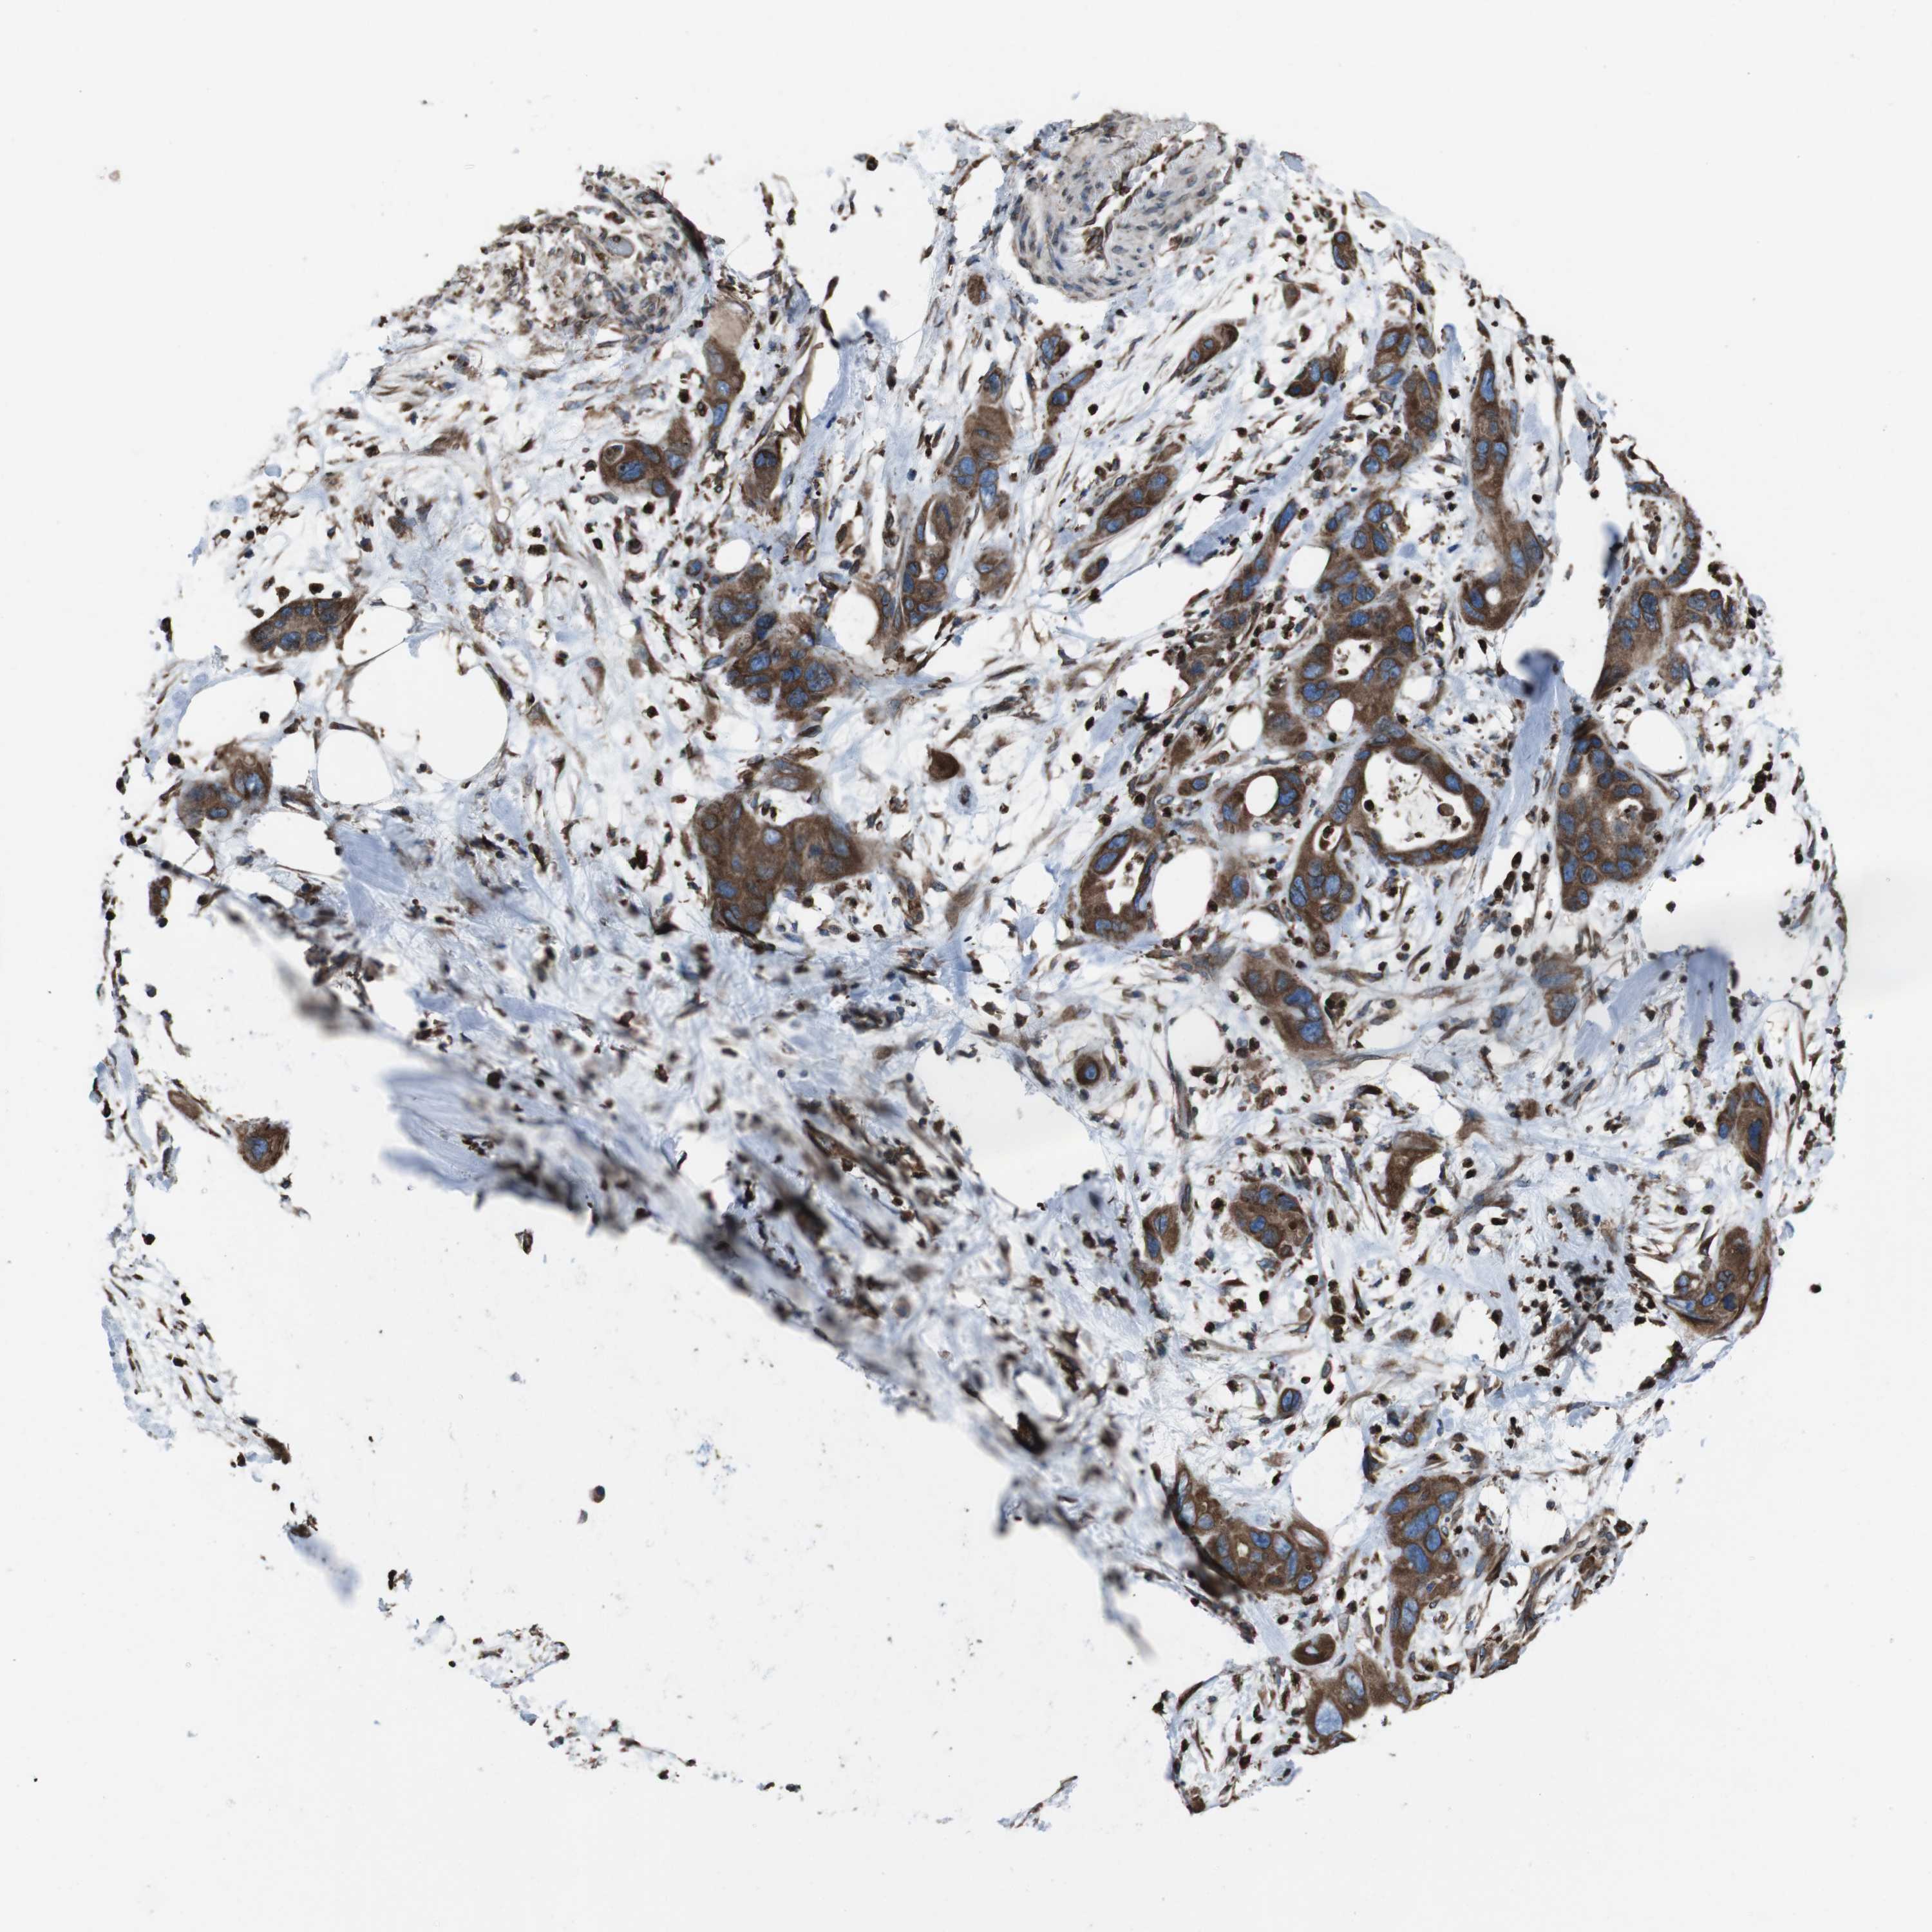

PANCREATIC CANCER - Protein expressioni

A mouse-over function shows sample information and annotation data. Click on an image to view it in a full screen mode. Samples can be filtered based on level of antibody staining by selecting one or several of the following categories: high, medium, low and not detected. The assay and annotation is described here.

Note that samples used for immunohistochemistry by the Human Protein Atlas do not correspond to samples in the TCGA dataset.

Antibody stainingi

Antibody staining in the annotated cell types in the current human tissue is reported as not detected, low, medium, or high, based on conventional immunohistochemistry profiling in selected tissues. This score is based on the combination of the staining intensity and fraction of stained cells.

Each image is clickable and will lead to virtual microscopy that enables deeper exploration of all samples and also displays staining intensity scores, fraction scores and subcellular localization as well as patient and tissue information for each sample.

Antibody HPA012863

Staining

High

Medium

Low

Not detected

Intensity

Strong

Moderate

Weak

Negative

Quantity

>75%

75%-25%

<25%

None

Location

Nuclear

Cytoplasmic/membranous

Cytoplasmic/membranous,nuclear

Adenocarcinoma, NOS